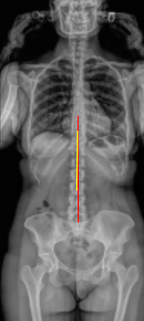

Full Length Spine

Coronal Balance

Apical Vertebral Translation (AVT)

Cobb Angle

Trunk Shift

Rib-Pelvis Distance